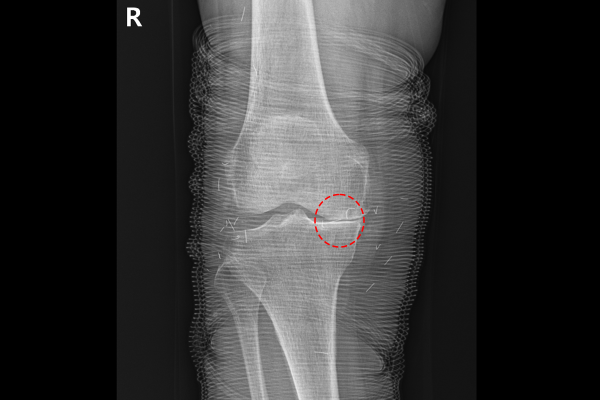

환자분의 무릎 상태를 자세히 파악하기 위해서 X-RAY 촬영을 진행하였고, 검사 결과, 우측 무릎 연골이 닳아서 안쪽이 달라 붙은 것이 확인되었습니다.